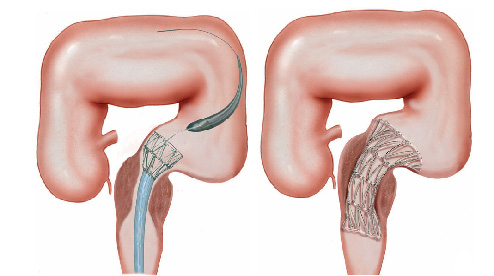

Tratamento e Processo

Estenose do esôfago é geralmente um problema mecânico, que pode ser tratada com o alongamento (dilatação). Isto pode ser feito de diferentes maneiras.

- Dilatadores flexíveis: uma série de sondas graduadas (espessura crescente) chamadas de sondas termoplásticas podem ser usadas. Estes são tubos que passam através do esófago para o estômago. Os tubos utilizados tornam-se progressivamente maior, até que o tamanho desejado seja atingido

- Balões dilatadores: a dilatação do esôfago pode ser feita usando balões durante a endoscopia. A endoscopia flexível permite ao examinador visualizar diretamente a estenose. Um balão é introduzido pelo canal do aparelho até a zona de estreitamento. Ele é então insuflado com água até uma certa pressão, que é pré-ajustada para uma dada circunferência. Quando insuflado, torna-se em forma de salsicha, esticado, e faz com que a estenose se abra.

Tratamento da Acalasia

- A Acalasia requer um tipo de balão específico, mais longo e maior, chamado de balão pneumático. Nesta situação, as fibras musculares espásticas na parte inferior do esôfago são esticadas.

Em alguns casos de acalásia pode-se tentar o tratamento com injeção de toxina botulínica (botox).

No casos de acalásia que não melhoram com dilatações por endoscopia o tratamento cirúrgico é indicado através do procedimento chamado de miotomia.

Estenoplastia

Em algumas ocasiões, o estreitamento (estenose) é tão grande que nem os instrumentos de dilatação conseguem passar. Nestes casos e em algumas outras situações, realiza-se o procedimento de estenoplastia. Este consiste na realização de pequenos cortes na região da estenose com auxílio de um estilete que é passado pelo canal de trabalho do endoscópio. Estes pequenos cortes ajudam abrir o estreitamento facilitando a passagem dos dilatadores e acelerando o processo do tratamento. Em alguns casos após a realização dos pequenos cortes algumas substâncias, como corticóides, são injetadas na região para prevenir que o estreitamento feche novamente com facilidade.

O que é o piloro ?

Piloro é o esfíncter que fica na poção final do estômago, na sua transição com o duodeno. Com os movimentos de contração do estômago o piloro se abre a permite que o conteúdo estomacal passe para o duodeno.

Estenose de piloro

Estenose do piloro é o estreitamento parcial ou total do mesmo que impede a progressão do conteúdo do estômago para o duodeno.

Estenose do piloro pode acontecer por 3 causas principais:

1- Estenose hipertrófica do piloro: condição que acontece em alguns recém nascidos onde o musculo do esfíncter fica muito “apertado” e impede que o conteúdo estomacal passe para o intestino. Nestas casos as crianças tem crises de vômitos e ficam desnutridas. A resolução deste problema é feita por cirurgia através do procedimento de piloroplastia.

2- Tumores do estômago: alguns tumores do estômago podem crescer ao ponto de causar a obstrução do piloro impedindo a progressão do conteúdo estomacal. Nestes casos geralmente realiza-se cirurgia para se retirar a parte do estômago acometida. Nos casos muito avançados pode-se passar através de endoscopia uma prótese autoexpansível para desobstrução.

Alguns casos onde a colocação da prótese não é possível realiza-se o procedimento de derivação gástrica, ligando o estômago com o intestino.

3- Estenose benignas: algumas úlceras do estômago ou do piloro podem ao cicatrizar levar a retração da parede do órgão e fechamento do piloro. Nestes casos realiza-se a dilatação endoscópica da região com balão do tipo hidrostático.

Nos casos onde não há melhora com as dilatações realiza-se o tratamento cirúrgico do problema.